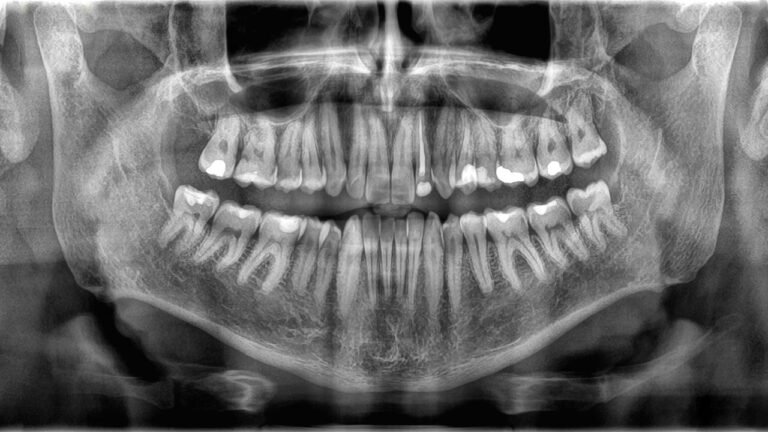

Because bones and teeth do different jobs, they’re also built differently. The outer structure of teeth is called enamel, a thin layer of mineralized tissue. Enamel is the hardest substance in the body — a property it gets from jam-packed crystals made from a compound of calcium and phosphate.

Underneath the enamel lies dentin, a type of mineralized tissue that’s slightly softer than enamel but still hard. Dentin makes up the majority of a tooth’s structure, and it contains tiny tubes that hold blood vessels and nerve endings. The core of the tooth is made of a jelly-like substance called pulp, which houses more blood vessels that provide nutrients to the tooth and to the nerves that control feeling in the tooth.